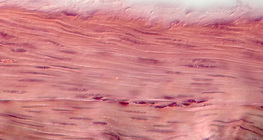

100 дахин томруулсан